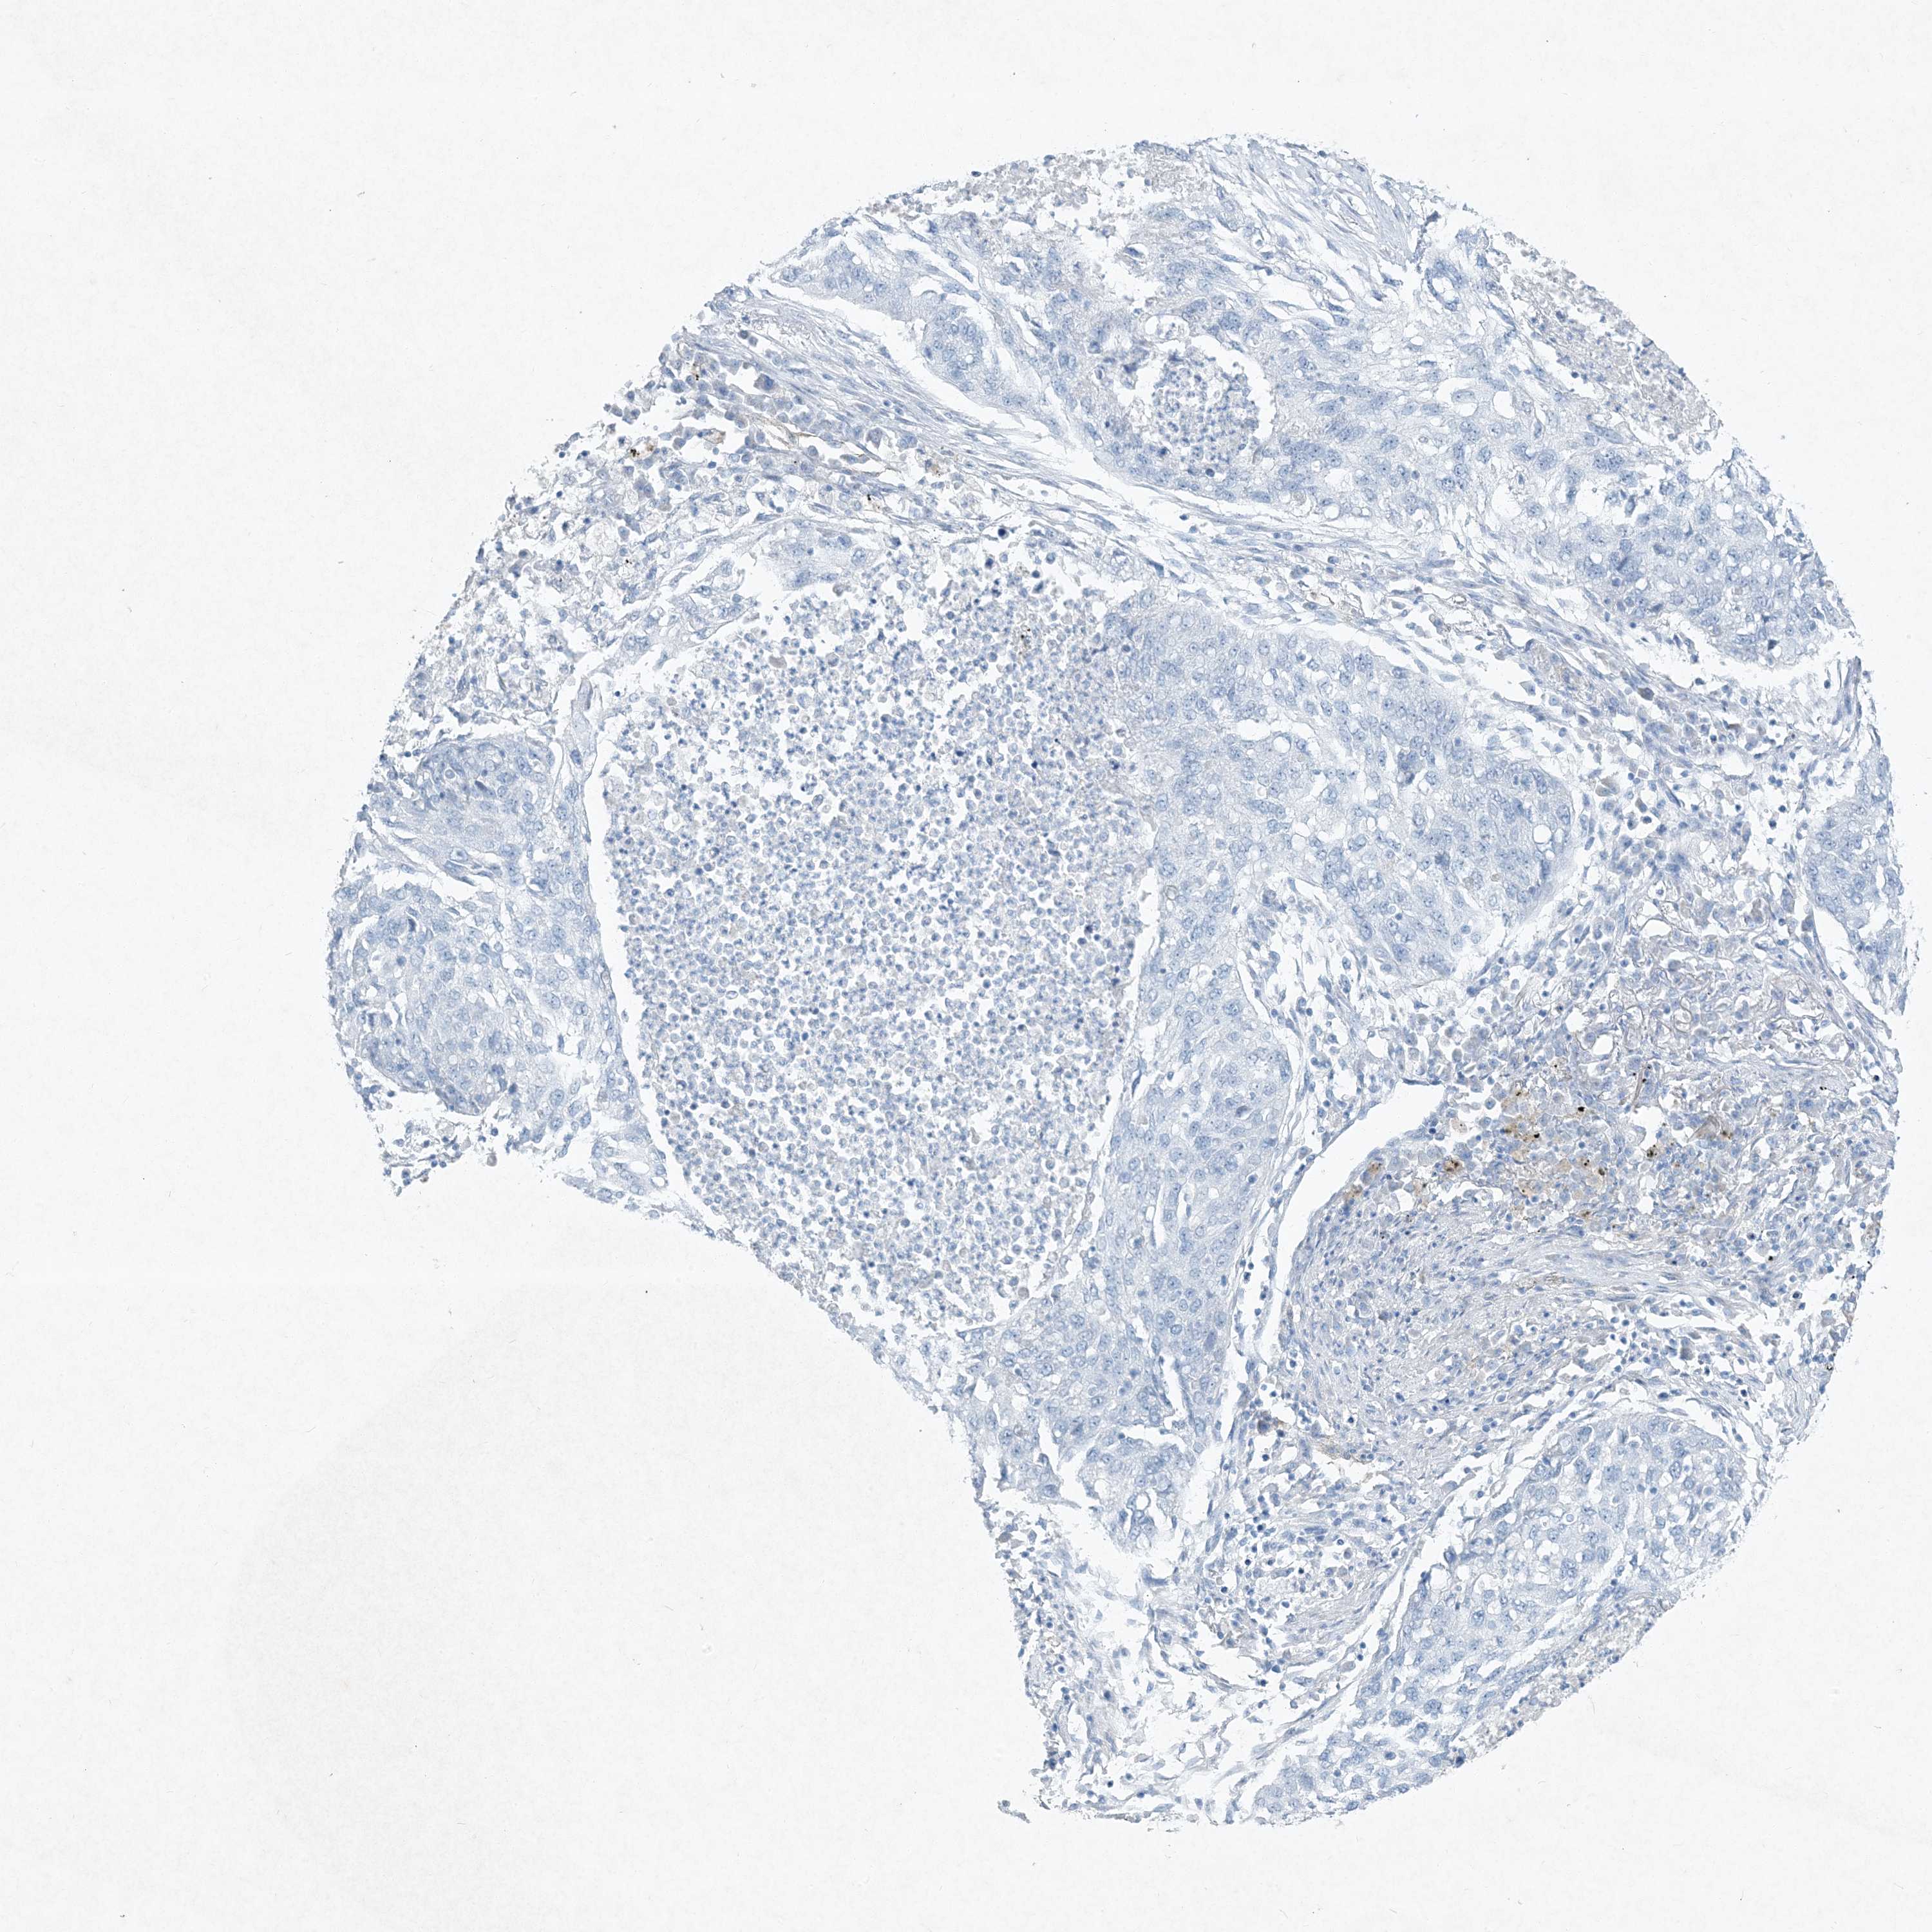

CANCER LUNG CANCER Show tissue menu